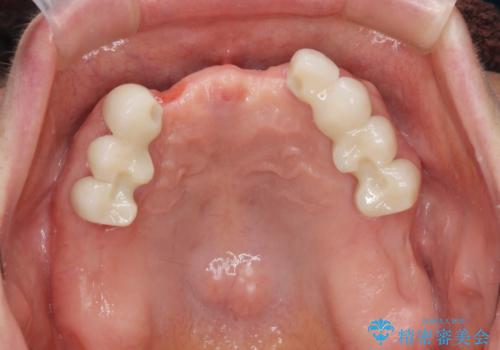

「大規模な手術は避けたい。」と言う希望を鑑み、インプラントではなく残せる歯の連結セラミッククラウンの作製、金属床義歯を用いてしっかりと咬合機能を回復できるよう治療を進めます。

- 110万円(ジルコニアクラウン×7・仮歯×7 金属床義歯)費用は治療当時の料金となります

年齢と体調を考慮して、インプラントではなく入れ歯で咬合機能の回復を達成する治療計画としました。